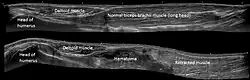

Musculoskeletal

Musculoskeletal ultrasound is used to examine tendons, muscles, nerves, ligaments, soft tissue masses, and bone surfaces.[45] It is helpful in diagnosing ligament sprains, muscles strains and joint pathology. It is an alternative or supplement to x-ray imaging in detecting fractures of the wrist, elbow and shoulder for patients up to 12 years[46] (Fracture sonography).